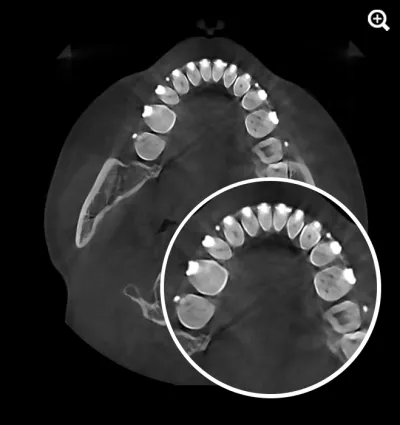

HDX WILL’s cutting-edge technology now offers a powerful solution through PrecisionMAR™, a metal artifact reduction feature that enhances clarity and ensures more precise imaging—even around metal. This is especially valuable for both dental professionals and ENT specialists focused on comprehensive treatment planning, including airway-focused care.

Minimizes scatter for cleaner imaging

Reduces shading and streak-related artifacts

Clearly defines bone and dental structures adjacent to metal

With improved image fidelity, practitioners can more confidently diagnose conditions, plan treatments, and support airway health initiatives critical to both dental and ENT fields.